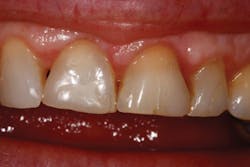

This patient came directly out of hygiene with a chipped tooth. The patient was aware that teeth Nos. 7-10 were in need of crowns. Tooth No. 8 was bonded (figure 1). The patient was informed that this was a temporary fix and agreed to schedule crowns for teeth Nos. 8 and 9. Due to wear, secondary to bruxism, teeth Nos. 8 and 9 had supererupted, bringing their gingival margins too far coronal for proper esthetics. A preprosthetic esthetic crown lengthening was suggested to ensure optimal esthetics. Orthodontic intrusion was also considered, but the patient was not interested. A mock-up of the results in gingival margin improvement was demonstrated with flowable composite. The patient preferred this option to surgery with a periodontist, which would have included a flap and four to six sutures. Soft tissue and approximately 2 mm of bone needed to be removed in order to reestablish proper gingival levels. This was an unscheduled case; the patient came right out of hygiene and requested to complete the crown lengthening procedure while she was in the office. She just wanted to be sure that it was still okay to meet her friend for lunch (it was, and she had sesame chicken).

Figure 1: Pre-op

Figure 2: Immediate post-op